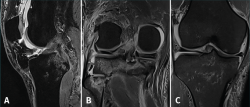

Magnetic resonance imaging (MRI) revealed multiple contusion edema zones with severe partial rupture of the ACL and grade I-II lesion of the PCL, with normal insertion at distal level (Figure 3A). In addition, proximal distension of the medial collateral ligament (MCL) and lateral collateral ligament (LCL) was observed, together with damage to the external meniscus posterior root (LaPrade type 4) (Figure 3B) associated to fracture of the external tibial plateau and deinsertion of the internal meniscus posterior root (LaPrade type 5) (Figure 3B) with meniscal extrusion (Figure 3C).

Figure 3. Magnetic resonance imaging study showing post-contusion edema of the tibia, with rupture of the anterior cruciate ligament. The posterior cruciate ligament appears correctly inserted in the sagittal view (A); the coronal view shows a radial lesion of the external meniscal root and bone avulsion with a bone fragment of the external root (B), causing extrusion of the internal meniscus (C).